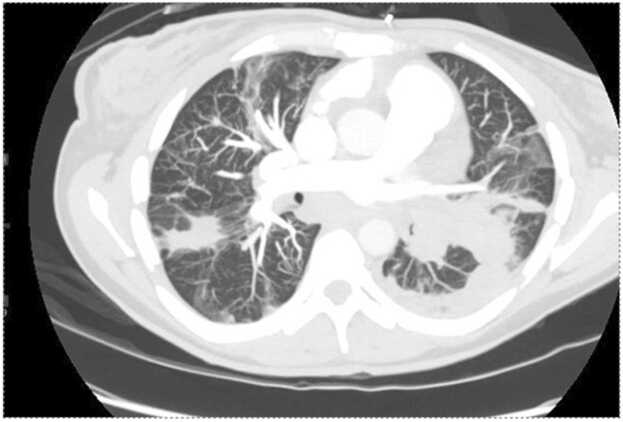

The patient represented two weeks later with hemoptysis and shortness of breath. She reported good compliance with her apixaban, and maintained sobriety on methadone 80 mg daily. Her TTE was again repeated and showed no vegetation, moderately reduced ejection fraction, and evidence of right heart strain with severe tricuspid regurgitation. Computer tomography pulmonary angiography showed only minimal improvement of extensive pulmonary artery emboli involving the left proximal pulmonary artery, the entire left lower pulmonary artery, and multifocal involvement of the right pulmonary artery (Fig. 2). There was also an increase in the size of consolidating opacities in the left upper and lower lobes consistent with worsening pulmonary infarcts. Based on the patient's extensive clot burden, inability to tolerate anticoagulation due to hemoptysis, and sustained sobriety, cardiothoracic surgery recommended pulmonary artery endarterectomy with concurrent tricuspid valve repair. The patient was transferred out of the hospital network for the procedure with follow-up pending.

Fig. 2.

Computer tomography pulmonary angiography showed diffuse pulmonary emboli and increased consolidative opacity in the left upper lung when compared to previous imaging, concerning for evolving pulmonary infarcts.